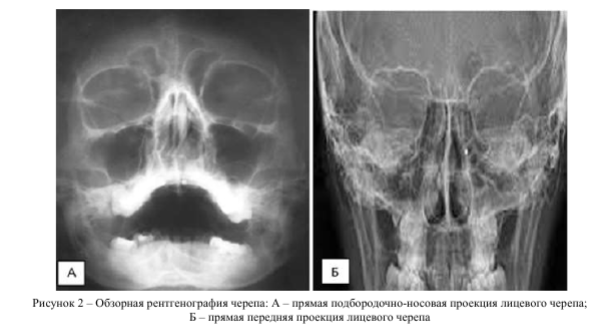

Всем пациентам проводили съемку черепа в передней прямой и боковой проекциях на рентгеновском аппарате «Униэксперт 3+» фирмы Ада- ни. Режимы работы 75 кВ, 32 мА^ ПФР 115 и эффективная доза 0,05 мЗв.

Рентгеновское исследование использовали в рамках первичной диагностики для визуализации костно-травматических изменений лицевого скелета, оценки изменений конфигурации стенок орбит, околоносовых синусов, носовой полости, видимых линий переломов. Косвенно оценивали мягкие ткани лицевого скелета при отёке мягких тканей или наличия вакуолей воздуха [7, 8].

При обследовании на дооперационном этапе всем пациентам (n=108; 100%) проводили анализ данных методов лучевой диагностики - обзорной рентгенографии, мультиспиральной компьютерной томографии согласно разработанному и расширенному протоколу описания повреждений костных и мягкотканных структур средней зоны лица.

Рентгенологическое исследование данной области позволило оценить нарушение целостности костей по следующим признакам: видимая линия перелома, нарушение гладкости контура кости и расхождение отломков костей в скулолобной (п=53; 49,1%), подглазничной (п=54; 50%), скулоальвеолярной областях (п=50; 46,3%). Увеличение объёма травмированной орбиты отметили в 32 случаях (29,6%). Также встречались косвенные признаки травматических повреждений средней зоны лица: затемнение верхнечелюстного синуса на стороне травматического воздействия (п=58; 53,7%) и в области мягких тканей средней зоны лица (п=56; 51,9%). Признаки инородных тел средней зоны лица и орбиты отметили у 10 пациентов (9,3%).

Детальную информацию о состоянии мягких тканей орбиты при использовании рентгенологического метода получить не удалось (рис. 2).

Для диагностики травматических повреждений костной глазницы применяют лучевые методы диагностики с применением ионизирующего излучения, а именно обзорная рентгенография черепа и мультиспиральная компьютерная томография (МСКТ).